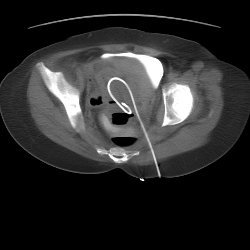

CT

Intervention